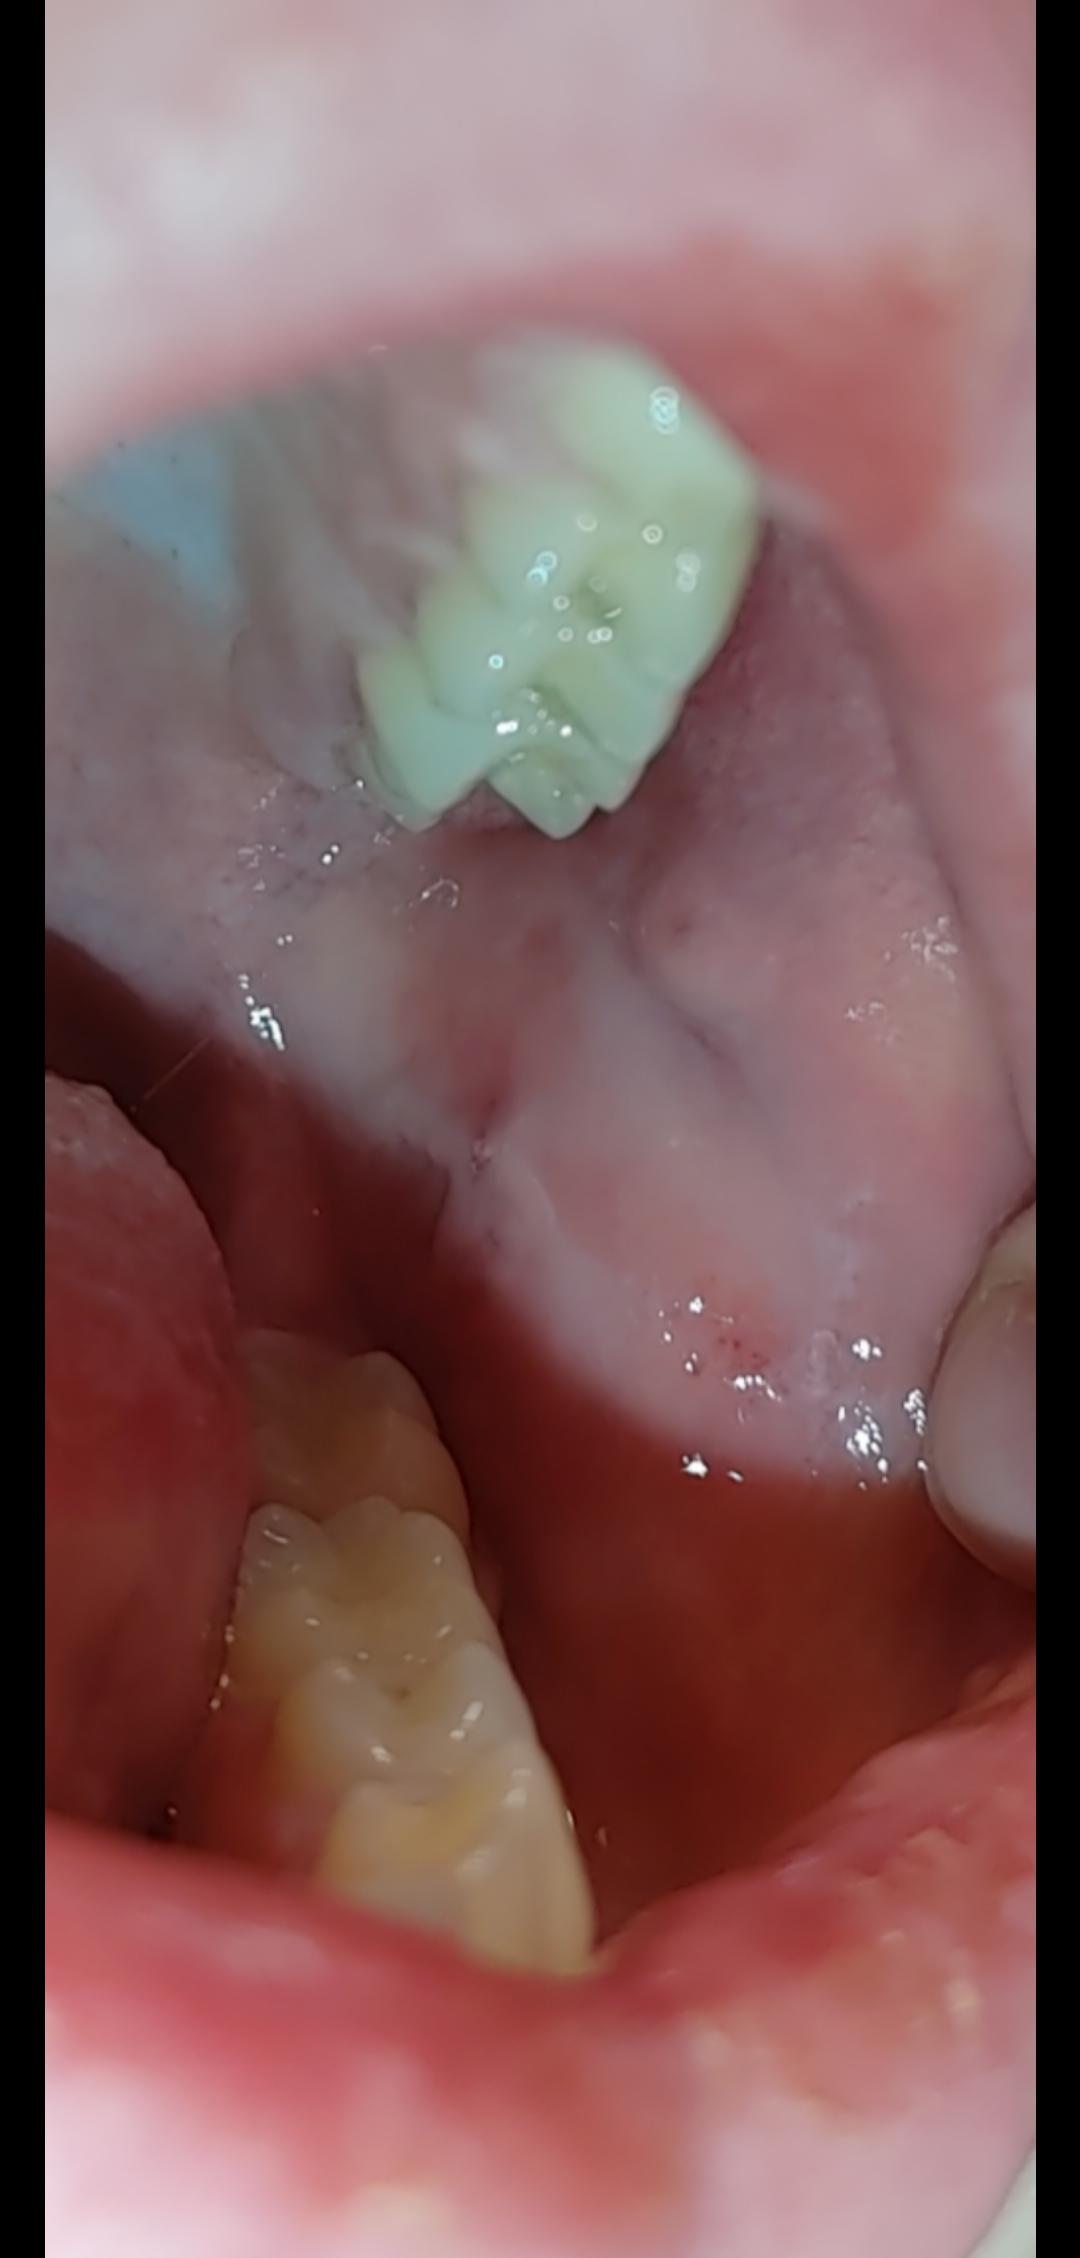

Common Causes of Mouth Pain & Swelling Berkeley, CA

i first noticed the pain in my mouth a few weeks ago, and just now Why Do I Taste Pain In My Mouth You may have a bad taste in your mouth due to something that you’ve eaten, dental problems, or other health conditions, including an infection or neurological issues. This article highlights some potential causes of a bad taste in the mouth and discusses its related symptoms and treatments. A long lasting salty taste can signal an underlying illness, infection, or. It. Why Do I Taste Pain In My Mouth.

From www.berkeleyhillsdentist.com

Common Causes of Mouth Pain & Swelling Berkeley, CA Why Do I Taste Pain In My Mouth Medically reviewed by stacy sampson, d.o. You may have a bad taste in your mouth due to something that you’ve eaten, dental problems, or other health conditions, including an infection or neurological issues. A long lasting salty taste can signal an underlying illness, infection, or. This article highlights some potential causes of a bad taste in the mouth and discusses. Why Do I Taste Pain In My Mouth.